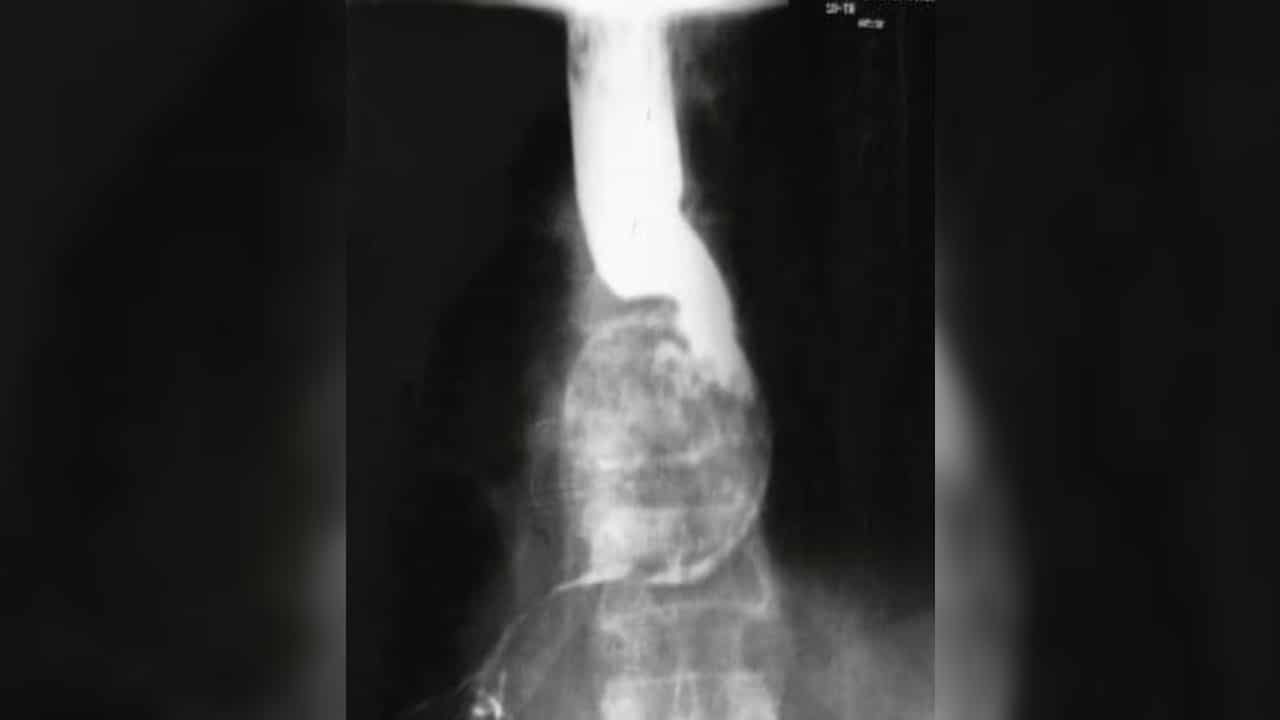

หญิง 70 ปี กลืนลำบากเป็นๆ หายๆ 4 ปี งวดนี้เป็นหนักเลยมา รพ. แพทย์ให้กลืนแร่ Barium แล้ว x-ray พบวัตถุปริศนาขดเป็นเกลียวในหลอดอาหาร สิ่งนั้นคือพยาธิไส้เดือน Ascaris lumbricoides เคสจากจีน ปี 2012

แพทย์ส่งตรวจกลืนแร่ barium ซึ่งเป็นสารทึบแสง แล้ว x-ray ปรากฎว่าพบก้อนรููปเกลียวอยู่ตำแหน่งหลอดอาหาร เหมือนมันขวางทางอยู่ แต่สารทืบแสงก็ผ่านลงไปได้นะ แสดงว่ายังมีช่องให้ผ่านไปได้